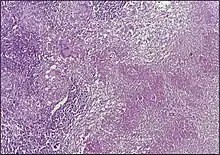

![]() | Follicular lymphoma | Micrograph showing a small B-cell lymphoma compatible with follicular lymphoma. H&E stain. | Category: Histopathology of follicular lymphoma | Follicular lymphoma |